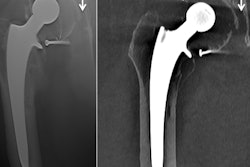

The configuration of the patient's hip joint often is distorted due to mechanical failure, the reaction at the interface between bone and the primary prosthesis, underlying osteoporosis, and hardware failure over time, explained the researchers, whose hospital is a tertiary referral center for patients with complex hip pathology and is one of the U.K.'s largest specialist young adult hip units.

Against this background, Dalili and colleagues decided to assess the value of 3D models of the hip joint in surgical care, utilizing current preoperative cross-sectional imaging modalities. They conducted what they think is the first study investigating the added value of 3D printing technology in complex THRs, and they are convinced this approach enhances surgical care preplanning, and has a potential effect on both short-term and long-term patient outcomes and health economics.

They prospectively collected preoperative CT data from 10 patients listed for complex revision hip arthroplasty (CRHA) and digitally reconstructed images using 3D printing software. All revision cases were discussed amongst three experienced hip surgeons and a musculoskeletal radiologist, who were asked to complete a short written questionnaire.

The level of complexity of the cases was ascertained by consensus among the surgeons. Thereafter, they were presented with the 3D model and asked to repeat the process and complete a written questionnaire about the proposed surgery, proposed prosthesis and size(s), expected operative time, expected recovery time, and degree of confidence in the details of proposed procedure, using a visual analog score (calibrated 0 to 10).